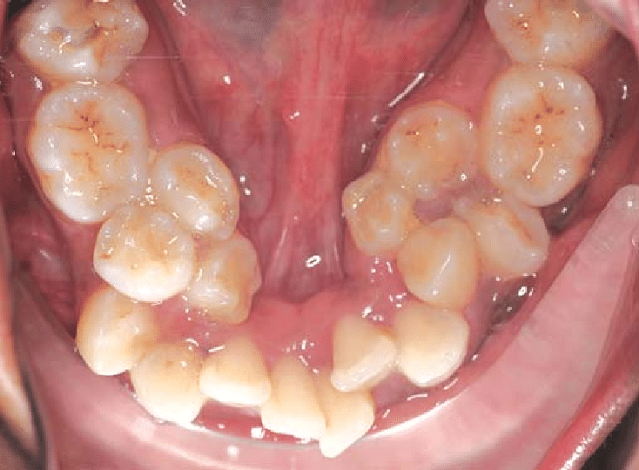

- Hypodontia: A significant proportion of individuals with OFDS exhibit hypodontia, specifically involving the lateral incisors.

- Supernumerary Teeth: These are extra teeth that can erupt in conjunction with the regular set, leading to crowding and misalignment.

- Delayed Eruption: Delays in the eruption of teeth can also be symptomatic, necessitating continuous dental monitoring.